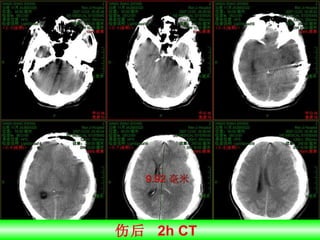

伤后  2h CT